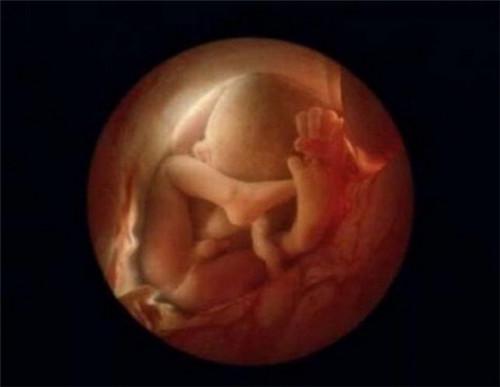

瑞士知名摄影师Lennart Nilsson花费10年时间拍摄一组照片,记录新生命孕育的全过程。Lennart Nilsson利用内窥镜可观察到胎囊内部从而获得更加精准绝美的照片。Nilsson将光导管与内窥镜相机连接,拍摄出数千张子宫内胎儿的照片,他灵巧的双手创造出了一个奇迹,向全世界展示了人类生命诞生的奥妙。

第20周。胎儿大约有20厘米长。头上开始出现头发

第36周。一个月后,婴儿将会来到世上。